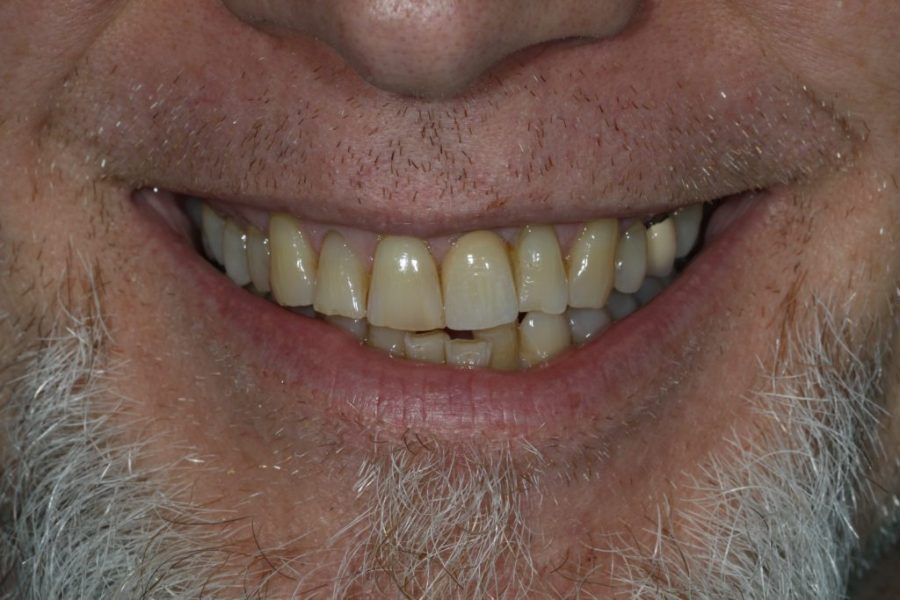

George’s Story: Customised Zirconium Bridges

George, hesitant at first, came to fix his front teeth at his wife’s insistence. After two appointments, he received zirconium bridges, giving him a full and natural smile—while preserving his signature gap.